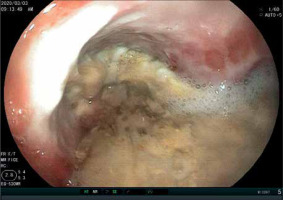

We registered 28 (15.9%) oesophageal complications (strictures) – 21 (75%) incomplete and 7 (25%) complete, and 22 (12.5%) stomach complications – 10 (45.5%) incomplete and 12 (54.5%) complete. Out of total strictures, 25 (64.1%) were on one location (either oesophagus or stomach), and 12 (30.8%) were on 2 locations (Figure 4).

Figure 4

Endoscopic finding of pyloric incomplete stricture in female, 21 days after of hydrochloric acid